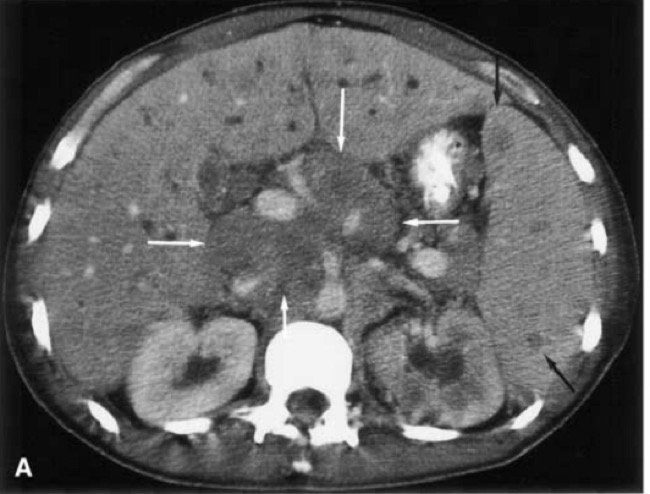

3. Solid Organs – Liver, Spleen, Kidneys

- Focal hypoattenuating masses

- Increase in size

4. Peritoneum/Omentum

- Thickening

- Nodularity

- Ascites